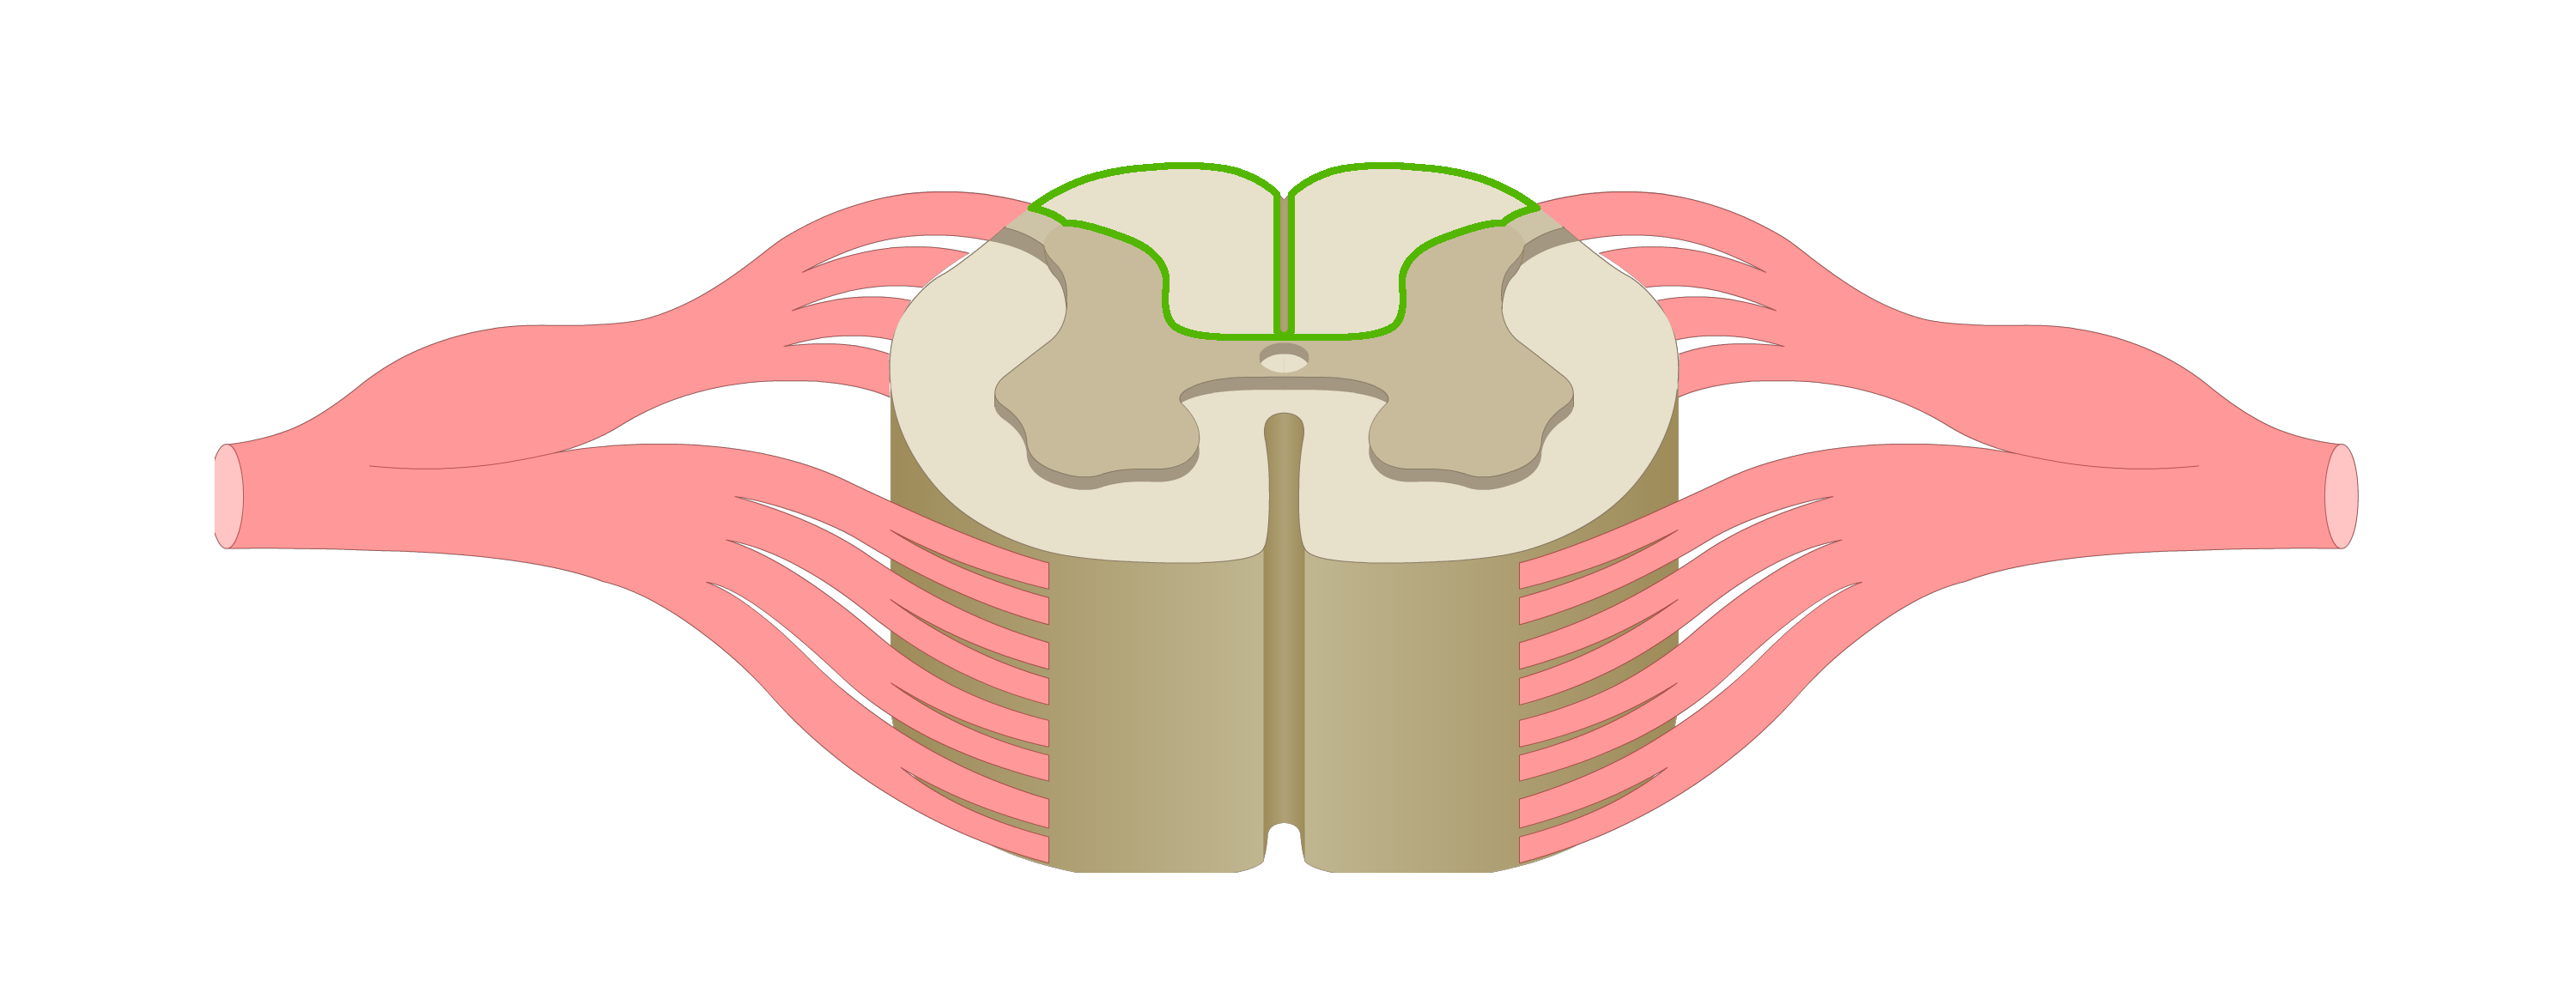

motor tracts

sensory tracts

dorsal root ganglion

dorsal horn

lateral horn

ventral horn

dorsal funiculus

lateral funiculus

ventral funiculus

central canal

ventral median fissure

dorsal median sulcus